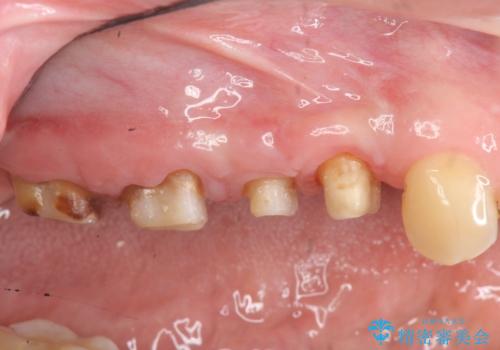

- 近医で「根尖の病変が大きく、残すことができない、歯を抜くしかない。」、と言われ歯を抜く以外の手段がないかを相談しに来院されました。

検査の結果、根管・クリアランス・虫歯といった複合的な問題が認められ、以下のような治療計画を進めることとしました。